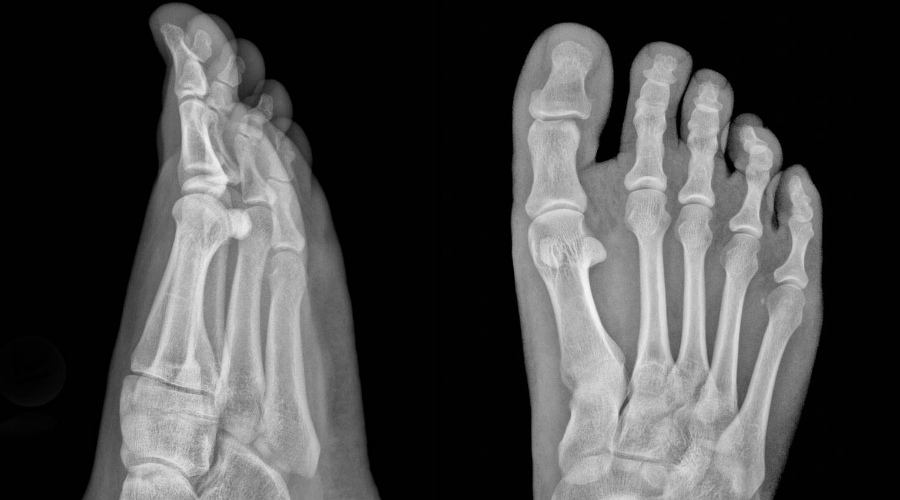

В здоровой стопе природное соединение подвижных костей составляет два свода. Они выполняют амортизирующую функцию. Врожденные пороки или внешние факторы могут привести к тому, что стопа становится плоской и соприкасается с поверхностью — соотвественно, амортизационная функция перекладывается на другие части тела, которые не предназначены для таких нагрузок. С этого и начинаются настоящие проблемы для всего организма.

Доведенное до третьей степени плоскостопие приводит к серьезной деформации стопы. Отеки появляются ежедневно, ходить становится трудно даже в пределах комнаты. Теперь без ортопедических ботинок обойтись не получится, иначе будет только хуже.